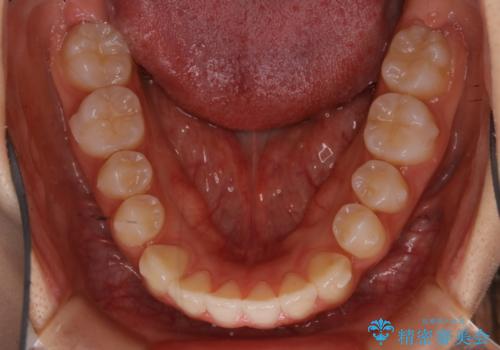

- 受け口の改善と前歯のガタつきの治療を主訴にご来院されました。

こちらの患者様の場合、上の前歯のガタつきが原因で口を閉じる際に上下の前歯の先端同士が先に当たってしまい、そこからさらに深く噛み込もうとすると下顎が前にずれていってしまうという、機能性の反対咬合であることが検査の結果わかりました。

そのため、まずは上顎の前歯のガタつきを改善していき、前歯が先に当たってしまうという症状を改善し噛み込む位置を後方の本来の位置に誘導する方法をとりました。